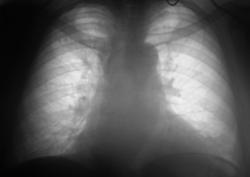

При расшифровке флюорограмм (иллюстрация 11) отметил наличие плотноватых очагов в 1 межреберье справа, некоторое усиление и обогащение легочного рисунка в базальных отделах, что собственно связано больше с возрастными изменениями, указал некоторое уплотнение стенки аорты, отметил снижение тонуса миокарда и «закрыл», «пошел дальше».

Внутри что-то дернулось, «вернулся» к приведенной иллюстрации. Еще раз пересмотрел с увеличением изображения (иллюстрация 12), обработал изображение при помощи функции «эквилизация», «прицепился» к мелким очаговым теням малой интенсивности вокруг вышеуказанных очагов, «взял на контроль» и успокоился.

Данное сообщение демонстрирует не только «коварство», вроде – бы, плотноватых очагов, но и иллюстрирует возможности «обработки изображения» с целью получения дополнительной информации